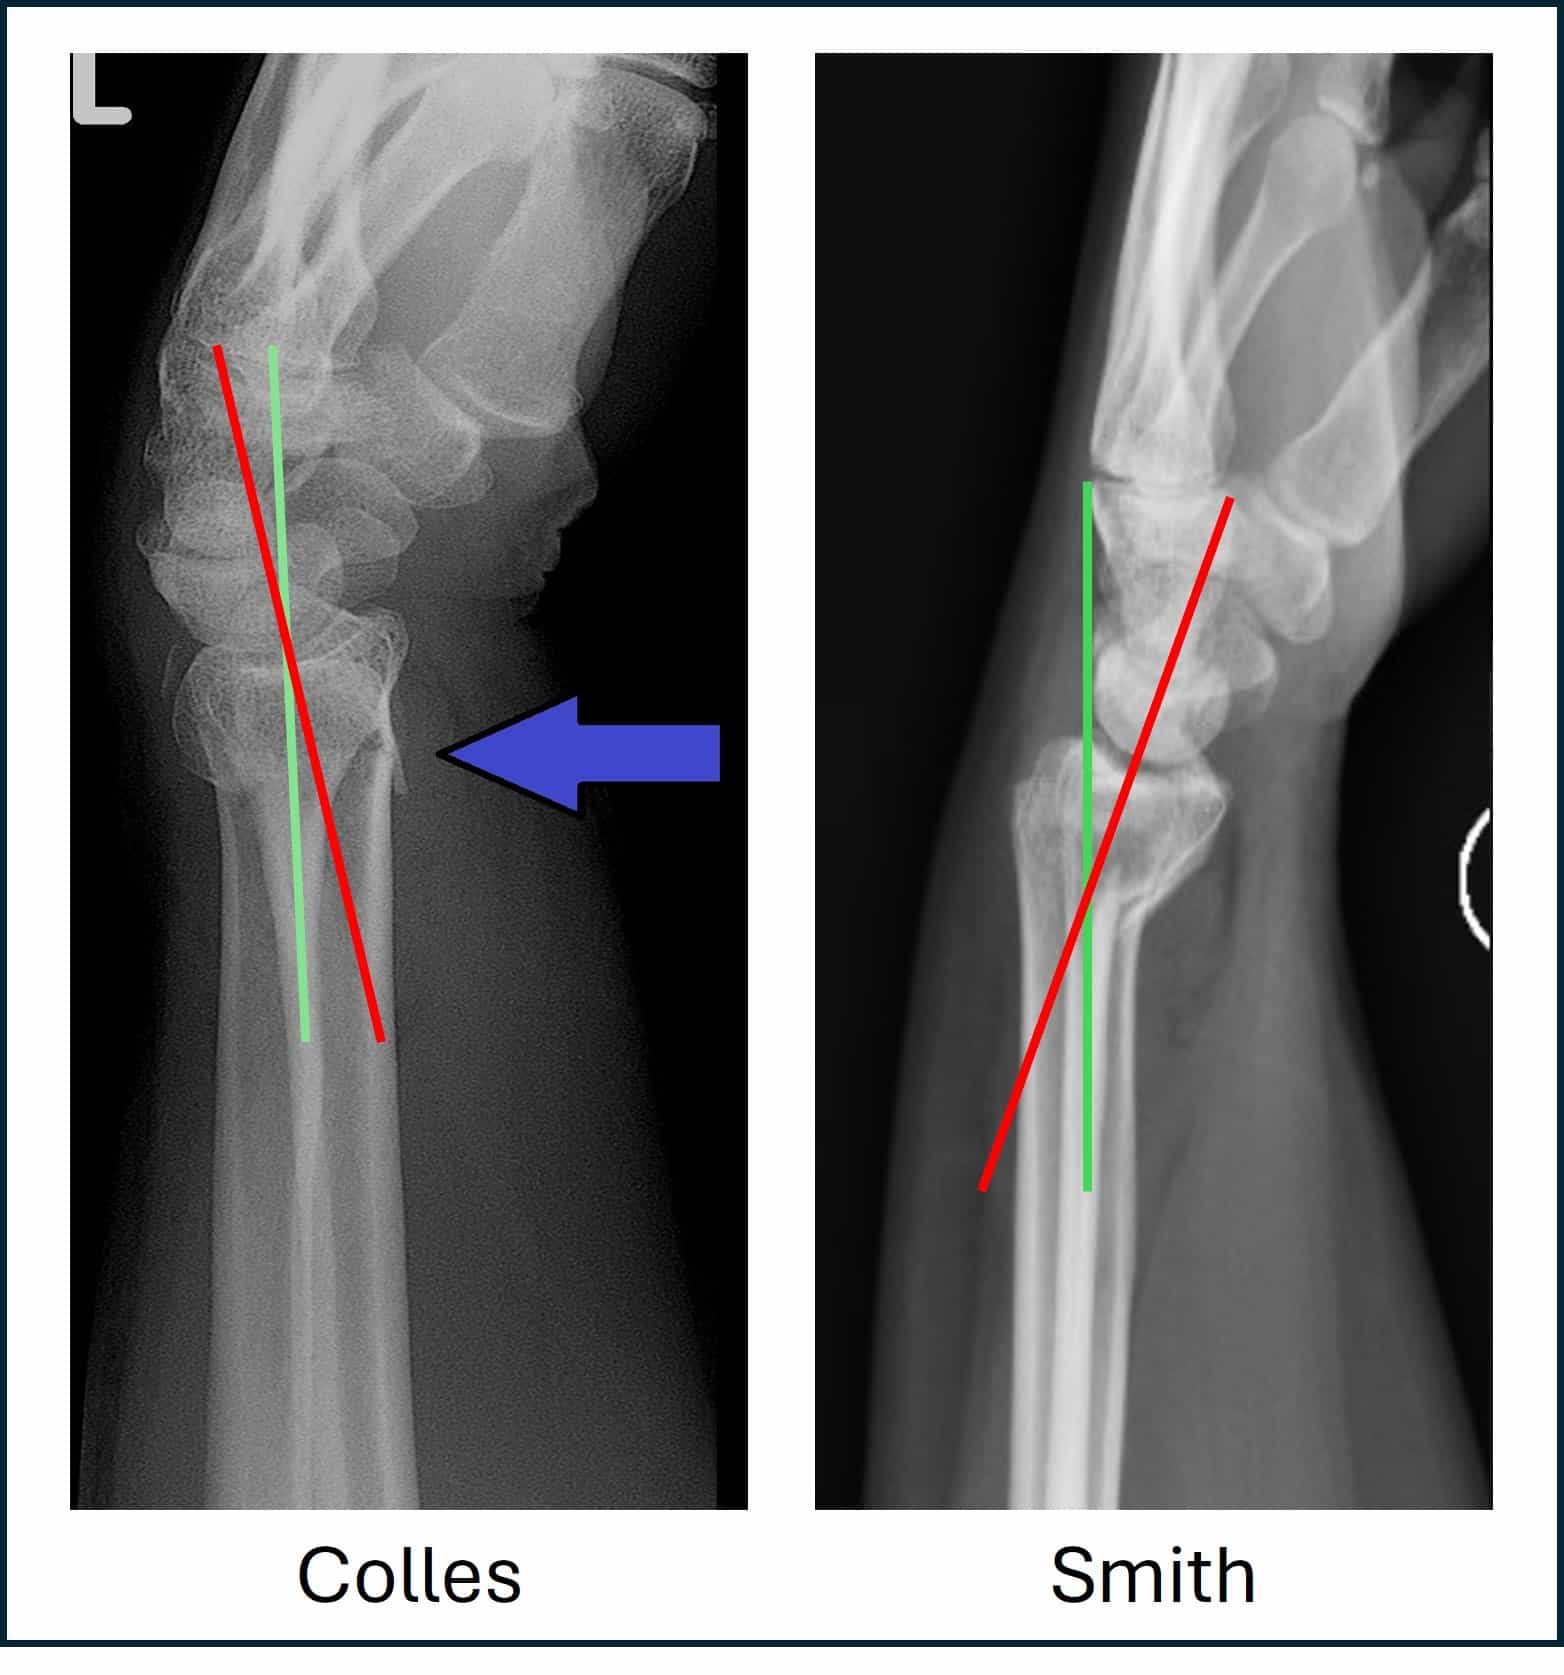

Suspect a dislocated pinky finger? Learn the common symptoms, immediate first aid steps, and effective treatment options. Discover when to seek urgent medical attention for a finger joint injury to ensure proper healing and restore full mobility. Get expert guidance on managing pain, reducing swelling, and promoting recovery for a safe return to normal hand function.